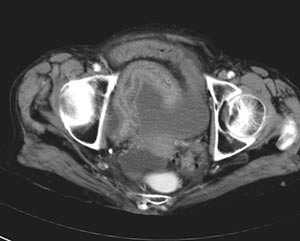

I motsetning til røntgen oversikt abdomen viste abdominal CT multiple luftvæskespeil i tynntarmen. Tynntarmslyngene var til dels moderat utspilte med diameter på om lag 3 cm (fig 1). Bak cøkum kunne man følge en slynge som ble innsnevret i forløpet, som ved obstruksjon. I tynntarmens videre forløp så man veggfortykkelse, økt kontrastoppladning i mukosa og halotegn. Mesenteriet viste stuvning og påfallende konvergens med antydet rotasjon som en virvel (whirl-sign, (fig 2, fig 3).

Funnet var forenlig med strangulasjonsileus, og indikasjonen for operativ behandling var nå åpenbar.